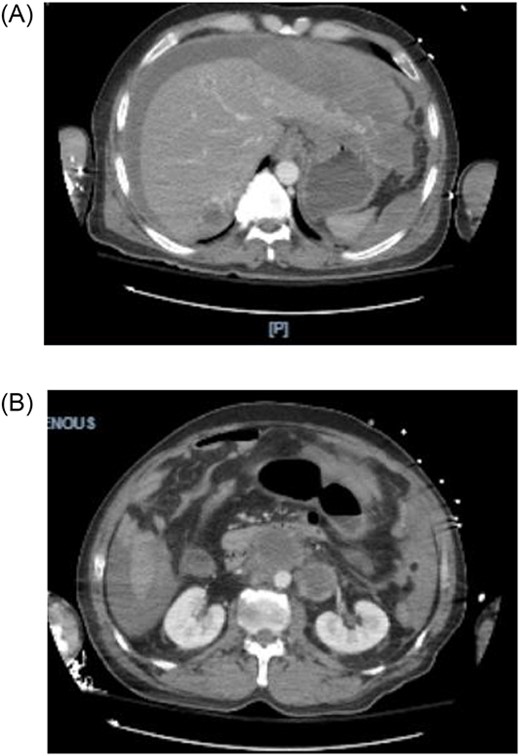

A 44-year-old male with a past medical history of alcohol abuse presented to the emergency department with 2 days of right upper quadrant abdominal pain and vomiting. The patient was reported to have hematemesis prior to arrival. The patient was unable to give a comprehensive history due to altered mental status and was noted to be diaphoretic, pale and hypotensive on arrival. Hemoglobin, hbg, was noted to be 10.1 upon arrival; however, subsequent hbg was 5.3. Bedside arterial blood gas showed significant metabolic acidosis with a pH of 7.03 and lactic acid of 11. Massive transfusion protocol was started and vasopressor therapy was initiated. Bedside Focused Assessment with Sonography in Trauma, FAST, exam was performed and positive for fluid in the right upper quadrant. At this time, the patient had been stabilized and the decision was made to obtain a computed tomography angiography (CTA) of the chest, abdomen and pelvis. CTA revealed hemoperitoneum anterior to the left lobe of the liver, a large para-aortic and aortocaval mass with peripheral enhancement suggesting neoplastic adenopathy, measuring 5.2 × 8.1 cm, and a complex septated lesion in the right scrotum (Fig. 1A and B).

(A, B) CTA shows hemoperitoneum anterior to the left lobe of the liver.